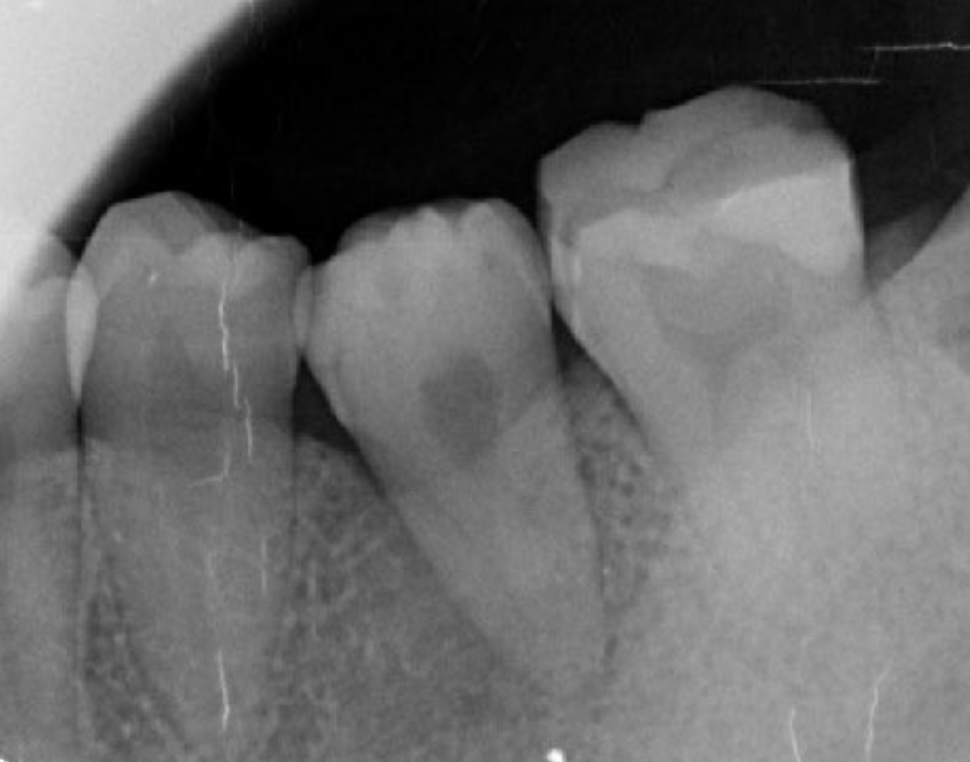

A 27-year-old female patient came to us with discomfort in the right lower jaw (Figure 1). Her primary symptoms were pain in the lower right tooth when biting and discomfort associated with not being able to chew well with the lower left single denture. The patient was married and had one young child, and previously received dental treatment in China, then had returned to Japan for childbirth and early childcare. The patient was a nonsmoker with moderate plaque control and medical history taking revealed no problems. In clinical and radiographic examinations, a root fracture was observed on tooth #46, which had been endodontic ally treated and restored with a full-cast metal crown. Periodontal probing revealed a pocket depth of 8 mm on the buccal center side of the tooth. No pain was detected with percussion and mobility of the tooth was normal. (Figure 1, Figure 2, Figure 3).

Figure 2.Pre-treatment X-ray findings. A cystic lesion was found in the mesial and distal roots apex, and root nodule of #46.